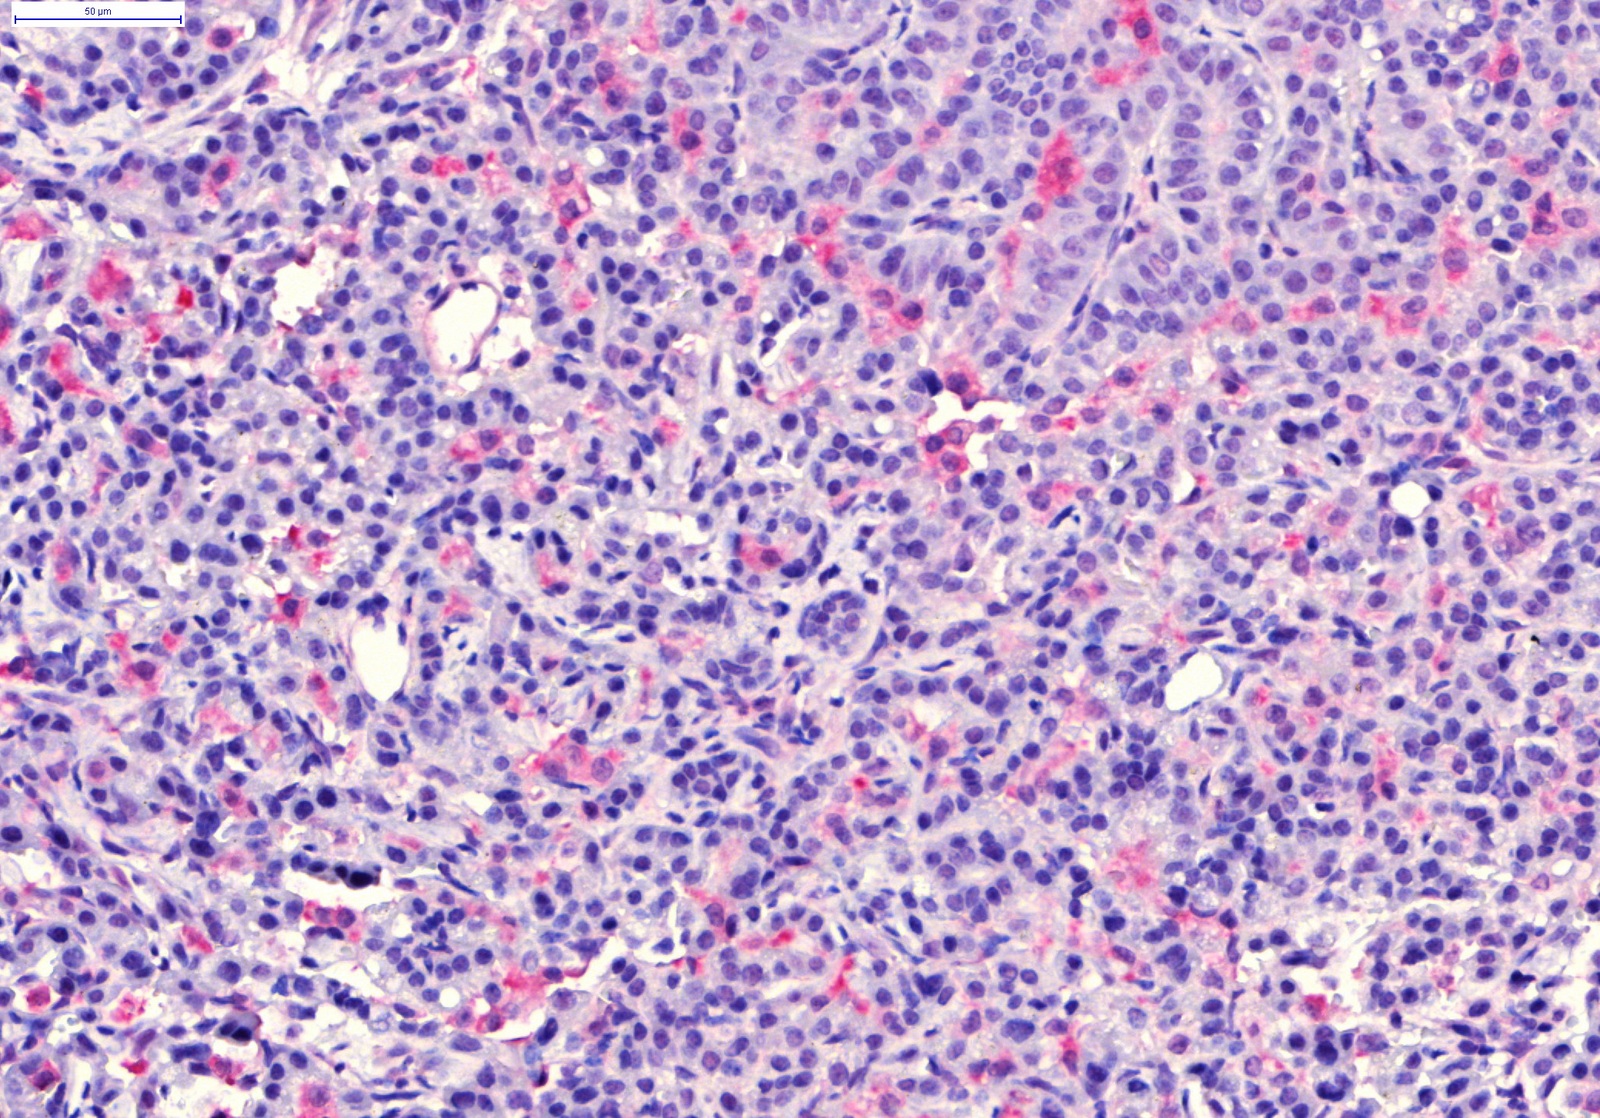

Günümüzde birçok nano bazlı ajanların hedefli tedavi yöntemleri ya da tanı amaçlı olarak kullanıma girdiğini ve birçoğunun ise hala klinik deney aşamasında olduğunu belirten Bölükbaş, "Bizim son yayımlanan çalışmamız mezoporoz silika nanoparçacıkları kullanarak akciğer kanseri tedavisindeki etkilerini görmeyi amaçlıyordu" dedi.

Çalışmanın ayırt edici tarafının, klinikte hali hazırda kullanılan fakat kemoterapinin sağlıklı akciğer dokusuna aşırı yan etkisinden dolayı çok da başvurulmayan bir tekniği (isolated lung perfusion) nanotıp bazlı bir ajanla ilk kez kullanmış olmaları olarak açıklayan Bölükbaş, şöyle devam etti:

Nanoparçacıklarımızın sadece kanser dokusunda toplandığını gösterdik. Üstelik yöntemimiz sadece akciğer dolaşımını hedeflediği için diğer organları da etkilemiyor. Böylece kemoterapiyi sadece kanser hücrelerine yansıtma fırsatımız doğuyor, yani normalde kemoterapiden zarar görecek sağlıklı hücrelere ilaç negatif etki etmeyecek. Şimdiki hedefimiz şu ana kadar sadece fare modellerinde kanıtladığımız bu etkiyi büyük hayvan modellerinde denemek.